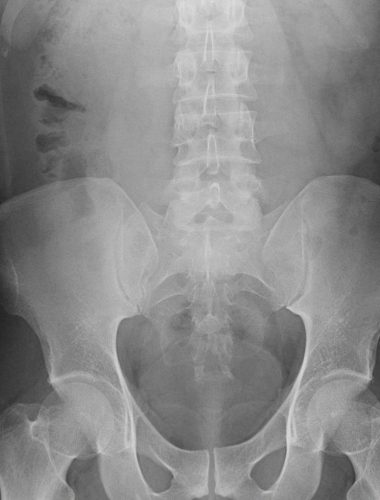

RX

A: Apendicolito

B: Borramiento psoas

C: Asa centinela

D: HiperDensidad de articulación sacroiliaca o FID derecha

E: Curvatura antiálgica